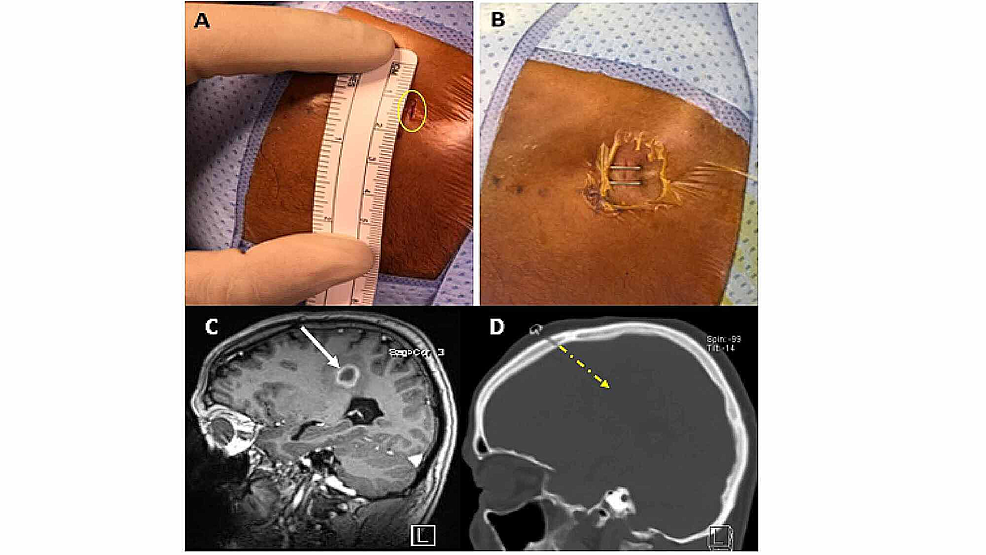

From www.cureus.com

Cureus A Simple Modified Technique for Frameless Brain Lesion Biopsy Mri With Staples In general, metallic orthopedic implants are not affected by mri. We have compiled a table listing the most. An mri scan uses a strong magnetic field and radio waves to create a detailed image. Mri stands for magnetic resonance imaging. Nhs ggc mri safety policy states that patients with skin staples i.e. Superficial skin staples and staples for internal wound. Mri With Staples.